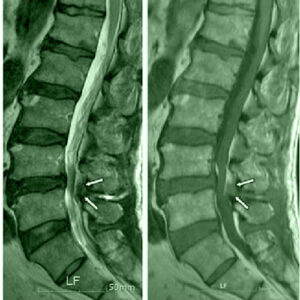

Ernia del Disco